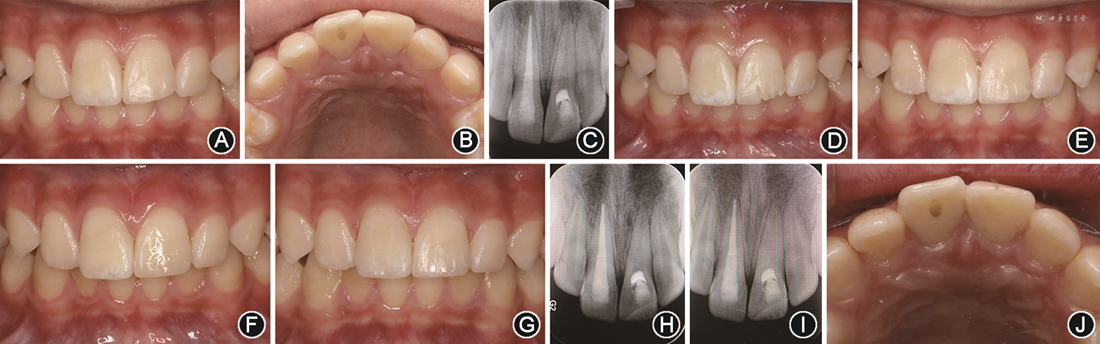

2.临床检查:患儿口腔卫生尚可,替牙列。11牙冠见两种折裂类型:①近远中向斜折,断冠已脱落,近中折断至龈下约1 mm,其余断面均位于龈上(图1A,B);②腭侧面垂直向纵折,折裂片松动Ⅱ度,在位且无明显移位,折裂线累及髓腔和近远中面至腭侧根面(图1C)。11露髓孔直径大于2 mm,牙髓冷测试痛明显,探痛(+),叩痛(+),松动Ⅰ度,无龈沟渗血。21牙冠自近中切角斜折至远中面,远中断面平龈,唇腭侧断面均位于龈上,露髓孔直径约1 mm(图1A,B),牙髓冷测试痛明显,叩痛(+),松动Ⅰ度,无龈沟渗血。就诊前11、21断冠于患儿口底唾液中保存,就诊后置于生理盐水中保存,11断冠可对位密合,21断冠不完整、对位不密合。

像;B:上前牙

面像;C:11腭侧折裂断冠,无移位脱落;D~G为锥形束CT检查,D:11冠折露髓,箭头示露髓位置;E:11腭侧冠根折,箭头示折裂线

方位置,累及髓腔;F:11腭侧冠根折,箭头示折裂线根方位置显示不清,约平齐牙槽嵴顶;G:21冠折露髓,箭头示露髓位置

方位置,累及髓腔;F:11腭侧冠根折,箭头示折裂线根方位置显示不清,约平齐牙槽嵴顶;G:21冠折露髓,箭头示露髓位置3.影像学检查:见图1D~G。锥形束CT显示11、21冠折及髓,牙根发育至NollaⅩ期,牙周膜间隙略增宽,未见明显根折。11腭侧折裂线

方累及髓腔,斜行走向深达根面,根方折裂位置显示不清,约位于釉质牙骨质界下方1 mm、平齐牙槽嵴顶水平。

4.诊断:①11复杂冠根折伴亚脱位;②21复杂冠折伴亚脱位。